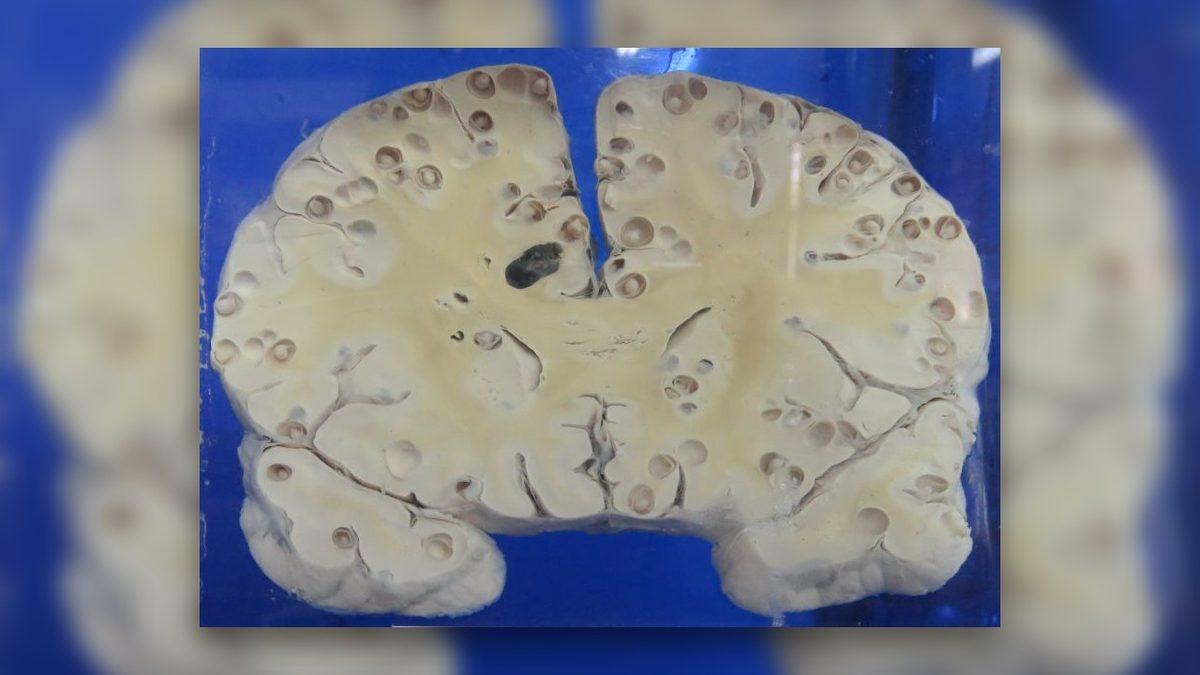

Adam 1 ay önce, az pişmiş domuz eti yemişti ve etteki parazit larvaları vücutta birikerek merkezî sinir sistemini istila etmişti. Zhu Zhong-fa’nın beyninde, akciğerlerinde ve göğüs boşluğunda 700’den fazla solucan kıvrıla kıvrıla geziyordu!

Nörosistiserkoz adı verilen bu enfeksiyona daha yakından bakalım.

Az pişmiş domuz etinin vücudumuza parazitler bırakmasıyla gelişen nörosistiserkoz; merkezî sinir sisteminde, kaslarda, ciltte ve gözlerde birikebilir. Az pişmiş domuz eti yiyen bir kişi, tuvalete gittikten sonra ellerini düzgün bir şekilde yıkamazsa mikroskobik solucan yumurtalarını yutabilir.

Yumurtaları yuttuktan sonra ise larvalar, yumurtadan çıkarlar ve bağırsak duvarına nüfuz ederek vücudun diğer bölgelerine yayılırlar. Böylece yukarıdaki beyin MR'ında görebileceğimiz manzaralar ortaya çıkabilir. Beyindeki ve vücudun diğer bölgelerindeki solucanları öldürmek için ilaç tedavisi uygulanır fakat nadir de olsa ölüme kadar gidebilir.